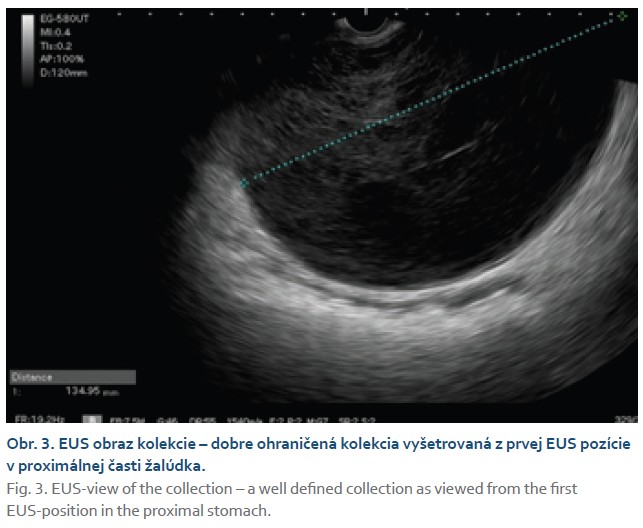

Samotný EUS výkon prebehol v monitorovanej celkovej anestéze. Terapeutickým echoendoskopom sa identifikovala dobre ohraničená kolekcia s nehomogénnym obsahom, ktorá odtláčala truncus coeliacus a ústie pyloru. V prvom kroku sa 19G ihlou Expect (Boston scientific, MA) aspiráciou získal slamovožltý až bezfarebný aspirát, ktorý sa odoslal na cytologickú a biochemickú analýzu. Následne po vylúčení interpozície ciev a v mieste najintímnejšieho naliehania kolekcie na stenu žalúdka (obr. 3) sa do kolekcie zaviedol 15/10- mm LAMS (Hot Axios, Boston Scientific, MA) pomocou čistého rezacieho prúdu (100 W) a po jeho uvoľnení sa pozoroval odtok sérosangvinolentnej tekutiny (obr. 4). Vzhľadom na tekutý charakter kolekcie sa výkon ukončil bez indexovej balónikovej dilatácie LAMS alebo zavedenia poistného koaxiálneho double-pigtail drénu. Po výkone došlo u pacientky k významnému zmierneniu ťažkostí, na ďalší deň bola realimentovaná, neboli zaznamenané žiadne periprocedurálne komplikácie. Biochemicky bol punktát charakteru exsudátu, kultivačne sme zachytili E. cloacae. Pokračovalo sa v ATB terapii dvojkombináciou metronidazol + kotrimoxazol podľa MIC, pri ktorej došlo k poklesu zápalových parametrov. Pacientka bola následne na vlastnú žiadosť prepustená do ambulantnej starostlivosti s odporúčaním klinickej kontroly. Vzhľadom na predpokladanú dĺžku dožitia bol LAMS zavedený ako definitívne riešenie a jeho extrakcia sa už neplánovala. Pacientka po 3 mesiacoch od zavedenia LAMS exitovala v domácom prostredí.